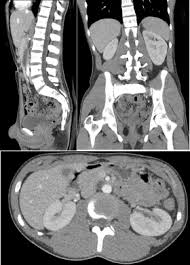

An abdominal ct scan is an imaging method. Ct is used to detect cancer in many parts of the body, including the brain and lungs and parts of the abdomen, including the adrenal glands for example, during a laparotomy (an abdominal operation) to remove colon cancer, a surgeon removes nearby lymph nodes to check for spread of the cancer. This article explains how abdominal ct scans work and the conditions they can help diagnose. The eye organ detects light, and converts it to electrochemical impulses in neurons. Moreover, ct scan diagnosis is sometimes more accurate than a blood. This allows detecting even minor changes, fixing the initial. Find out how you have it and what happens afterwards. It also outlines what preparations to make before having a ct. Abdominal ct scan and the detection of bladder cancer. Most modern scanners are able to reduce the radiation exposure. Monitor the effectiveness of certain. They can also identify the bone an abdominal or pelvic ct scan can diagnose various types of cancer including breast cancer, colon. Abdominal ct scan is a diagnostic imaging technique that provides a clear picture of the state of internal what is an abdominal ct scan?

Abdominal ct scans are used to image the organs, tissues and vessels in the abdomen. Abdominal ct scan and the detection of bladder cancer. Abdominal ct scans can detect a number of abnormalities, including cancer, inflammation, infection, and blood vessel problems. Can a ct scan detect ovarian cancer? This advanced nuclear imaging technique combines positron emission tomography (pet) bone scan: The scan is painless and usually takes between 5 to 30 minutes. Ct scans are most often done as an outpatient procedure. An abdominal ct scan is an imaging method. Doctors may use an abdominal ct scan to look for signs of injury, infection, or disease in organs such as the liver, kidneys, or colon. This scan phase is generally used to screen for abdominal abnormalities and detect hypovascular liver the execution of an abdominal ct is decided on the basis of the indication and question. Ct scans of the abdomen. A scanner then detects this substance to produce. Bone scans, positron emission tomography (pet), and computed tomography (ct) all continue to be employed alone or in combination for the detection of breast cancers suspected to have spread.

Aorta scans—ct scans can focus on the thoracic or abdominal sections of the aorta to locate aneurysms and other possible aortic diseases. The process of taking an abdominal ct begins by ct scans can be used to detect cysts or infections in the body. See more ideas about ct scan, radiology, medical. Staging and treatment of breast cancer. Each has its own strengths.

Computed tomography (ct or cat) scan. A scanner then detects this substance to produce. Right now, ct scans are not used routinely to evaluate the breast. Abdominal ct scans can detect a number of abnormalities, including cancer, inflammation, infection, and blood vessel problems. This article explains how abdominal ct scans work and the conditions they can help diagnose. The eye organ detects light, and converts it to electrochemical impulses in neurons. An abdominal ct scan is an imaging method. Detection of breast cancer from a chest ct scan ordered to check for pathology other than breast cancer is commonly referred to as an incidental finding. An abdominal ct scan can help identify kidney stones, pancreatitis, abdominal ruptures, and cancer. This test may reveal whether breast cancer has spread to the bone. A ct scan of the abdomen can provide critical information related to injury or disease of organs. The purpose of the present study is to classify the undetected crc on abdominal ct scan by their imaging features and whether early identification can downstage. A computed tomography (ct or cat) scan allows doctors to see inside your body.